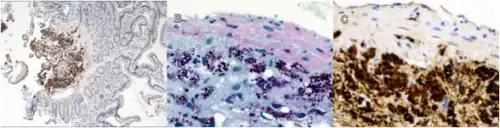

| Tropheryma whipplei bacteria in human macrophages | |

While T. whipplei is categorized with the Gram-positive Actinomycetota, the organism is commonly found to be Gram-positive or Gram-indeterminate when stained in the laboratory.[1] Whipple himself probably observed the organisms as rod-shaped structures with silver stain in his original case.[4]